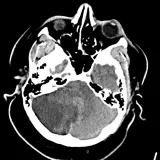

Over 2,100 interactive radiology cases, curated by radiologists for your level of training. Scroll, window, and view cases full screen — just like on PACS. Click linked findings in each writeup to jump straight to them on the image. Cases include sample reports, a focused discussion section, original illustrations, and videos.

Neuro Fellowship — a course tailored for fellows and practicing radiologists with in-depth reviews of advanced neuro topics like brain tumors, featuring rare diagnoses, differentials, and clinical pearls.

Casos totalmente interactivos con las herramientas que esperaría de un PACS: scroll, ventana, zoom, pan, mediciones, ROI y modo de pantalla completa.

• Anotaciones enlazadas

Anotaciones extensas resaltan los hallazgos clave directamente sobre los casos. Haga clic en los hallazgos enlazados dentro de la descripción del caso para saltar a su ubicación exacta en el estudio.